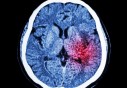

Le nombre de décès liés au COVID-19 aux Etats-Unis a dépassé mardi les 270.000, selon le Centre pour la science et ingénierie..

Neuf cent cinquante trois (953) nouveaux cas confirmés de Coronavirus, 596 guérisons et 16 décès ont été enregistrés durant les dernières 24 heures en Algérie, a annoncé, mardi à Alger, le porte-parole..